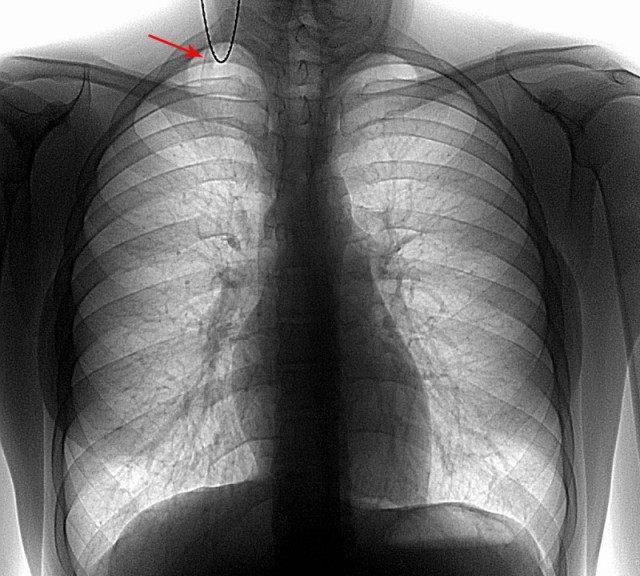

Дополнительные ребра

Обычно у среднестатистического человека имеется по 12 ребер с каждой стороны, но у некоторых людей встречается дополнительное ребро, которое, кстати, может вызывать проблемы со здоровьем.

Это ребро называется шейным, и встречается у 0,05–3 процентов людей, как показали исследования. Оно растет из основания шеи чуть выше ключицы, и иногда не формируется полностью, а состоит лишь из тонкой полоски волокна ткани.

Дополнительное ребро может привести к проблемам со здоровьем, если оно давит на близлежащие кровеносные сосуды или нервные окончания. Это приводит к состоянию, известному как синдром грудного выхода, для которого характерны боли в плече или шее, чувство потери конечности и наличие сгустков в крови.